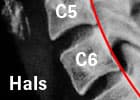

In den meisten Fällen liegt die Blockierung eines oder mehrerer Wirbelgelenke der HWS und/ oder der oberen BWS vor. Die HWS ist nur so weit beweglich, wie es die anderen frei beweglichen Gelenke erlauben. Häufig liegt eine Bandscheibendegeneration vor, die aufgrund einer chronischenÜberlastungsreizung der Wirbelgelenke einen Verschleiß in diesen Gelenken ausgelöst hat (Wirbelgelenksarthrose - Spondylarthrose oder Facettenarthrose).